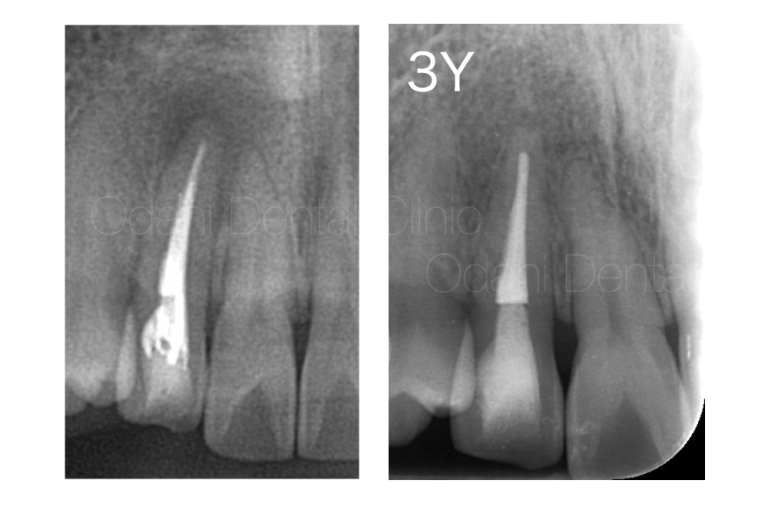

CTとマイクロスコープにより隠れた根管を発見して治療した症例 1年経過

症例プロフィール 来院までの背景 最近奥歯が噛むと違和感があるということで健診希望のため来院されまし...